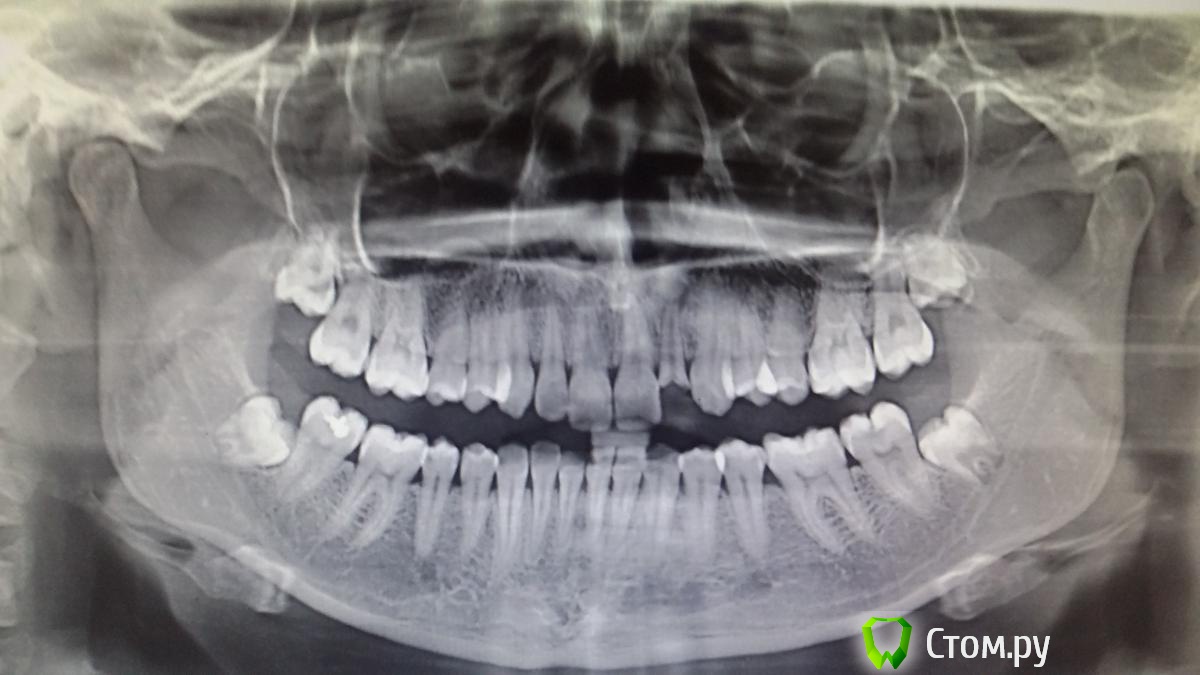

Recive Опубликовано 1 ноября, 2014 Поделиться Опубликовано 1 ноября, 2014 Обратилась с жалобами на скол зубаранее(со слов пациентки 1 год назад) лечила в государственной клинике.в кк паста, эндометазон или резорцин формальная, корень зуба изменен в цвете.Товарищи вопрос:рационально ли протезирование после резекции верхушки зуба?сколько там останется корня ? Назначил на кт.Хирург боится имплантировать отсроченно., боится сростания гребня и отсутствия кости. Ссылка на комментарий

Евгений Ходыкин Опубликовано 2 ноября, 2014 Поделиться Опубликовано 2 ноября, 2014 Фото во рту требуется. ИМХО ферула тут нет практически. Укк тут не катит, разве что ортодонтически вытянуть попробовать... 2 Ссылка на комментарий

Сева северный Опубликовано 23 ноября, 2014 Поделиться Опубликовано 23 ноября, 2014 Я за простые решения ...судя по снимку пломбированием и не пахло? Да и здоровый дентин и ферул видимо присутствует.Учитывая возраст консервативная тактика предпочтительна. Эндолечение через гидроокись. 2 недели ..ЕСЛИ ВСЕ СПОКОЙНО..Постоянное пломбирование. культевая вкладка, коронка .Контрольный снимок через пол года. Все! Лет на 15 должно хватить. Ссылка на комментарий